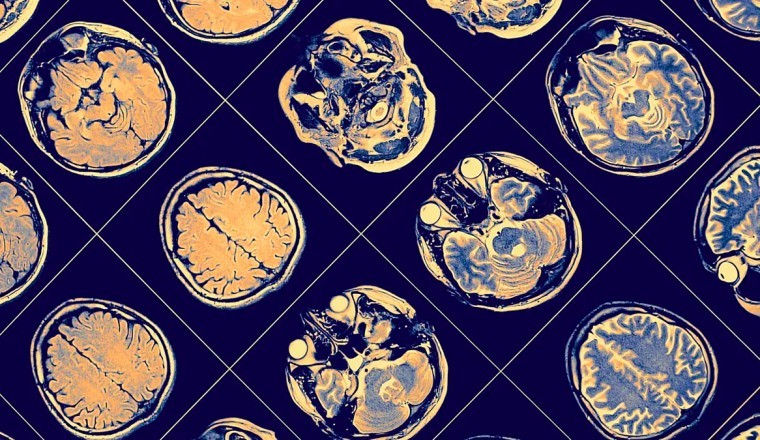

Để đưa ra kết luận này, các nhà khoa học đã nghiên cứu thông tin chụp cộng hưởng từ của 40 người đàn ông làm bố lần đầu. Một nửa trong số họ sống ở Tây Ban Nha, còn lại sống ở Mỹ. Nhóm đối chứng gồm 17 người chưa làm bố ở Tây Ban Nha.

Các ông bố Tây Ban Nha được quét não hai lần: trước khi bạn đời của họ mang thai và sau khi họ có con đầu lòng. Nhóm ở Mỹ được quét não từ giữa đến cuối thai kỳ của bạn đời và sau khi có con khoảng 7 đến 8 tháng.